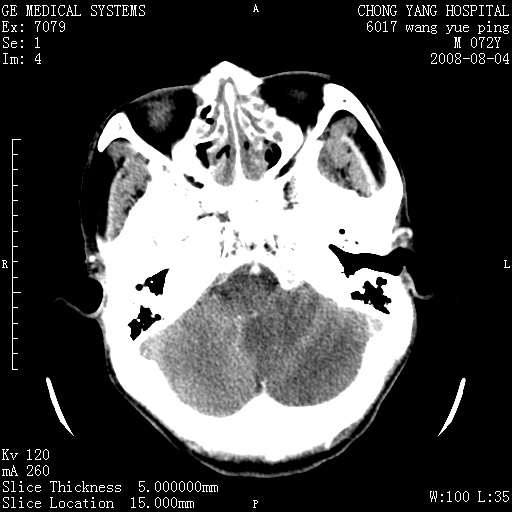

标题: CT14987:M72Y,头痛头昏,BP220/110. [打印本页]

1)考虑左侧小脑脑梗塞。2)脑白质病。3)脑萎缩。4)双侧鼻腔新生物(息肉?)并阻塞性副鼻窦炎。

1.左侧小脑大面积梗塞;2.左侧基底节区腔梗;3.白质疏松;4.脑萎缩;5.慢性副鼻窦炎

小脑左侧病灶呈扇形分布,增强后未见明显瘤体样节结影,病变区未见强化。

支持:左侧小脑脑梗塞梗塞表现

另:脑白质病。脑萎缩。双侧鼻腔新生物(息肉?)并阻塞性副鼻窦炎。

1)考虑左侧小脑脑梗塞,建议治疗后复查除外其他,左基底节区腔隙性脑梗塞2)脑白质变性3)脑萎缩。4)双侧鼻腔新生物(息肉?)并阻塞性副鼻窦炎。